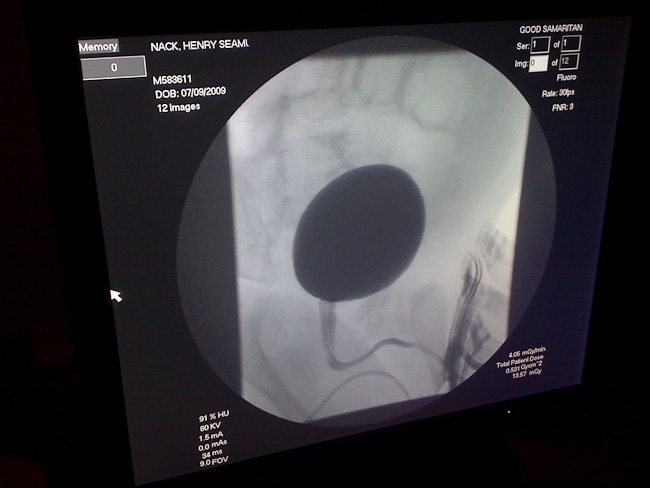

John & Margot Nack